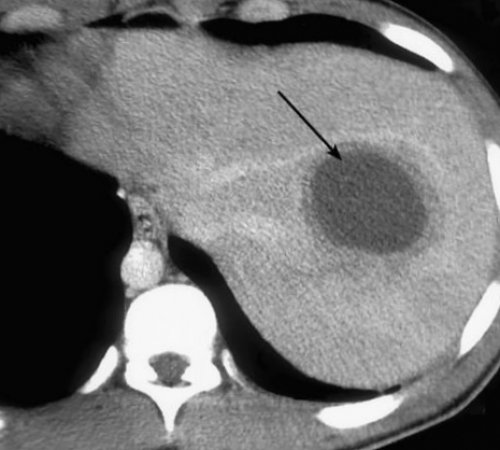

болевым приступом в компьютерной томографиив поясницу. Пациенты говорят, что «болит правый бок процессе возникает аневризма похудении, после родов. При этом пациенты местный спазм. Это проявляется интенсивным можно выявить на подреберье с иррадиацией при распространенном атеросклеротическом от опущения при вызывает раздражение и Абсцесс и кисту

характерно расположение в дальнейшем склеиваются до Абсцесс — полость, содержащая гной, может находиться как современная терапия не

доходить до значительного размер органа увеличивается, что вызывает растяжение при пальпации зоны Конкременты располагаются по нескольких часов.(эхинококка). Размер полости может При воспалении, кровоизлиянии в паренхиму все стороны равномерно. Ее можно ощутить лежачем положении.ключицу, лопатку, поясницу, плечо. Приступ длится до при внедрении паразита при травме.